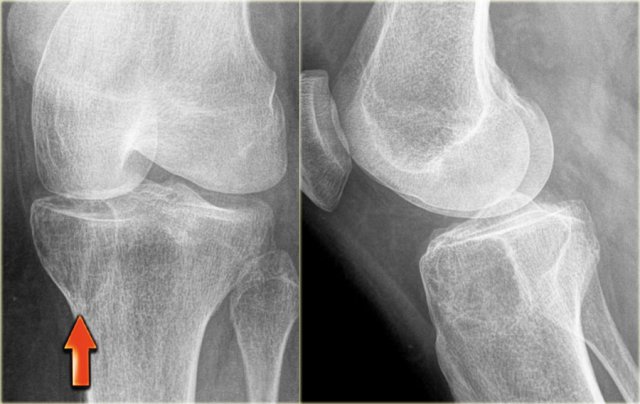

Giant cell tumor

Giant cell tumor is a lesion with multinucleated giant cells.

In most cases it is a benign lesion.

Malignant GCT is rare and differentiation between benign or malignant GCT is not possible based on the radiographs.

GCT is also included in the differential diagnosis of an ill-defined osteolytic lesion, provided the age and the site of the lesion are compatible.

Discriminators:

- Epiphyses must be closed.

- Must be an epiphyseal lesion and abut the articular surface.

- Must be well-defined and non-sclerotic margin.

- Must be eccentric.